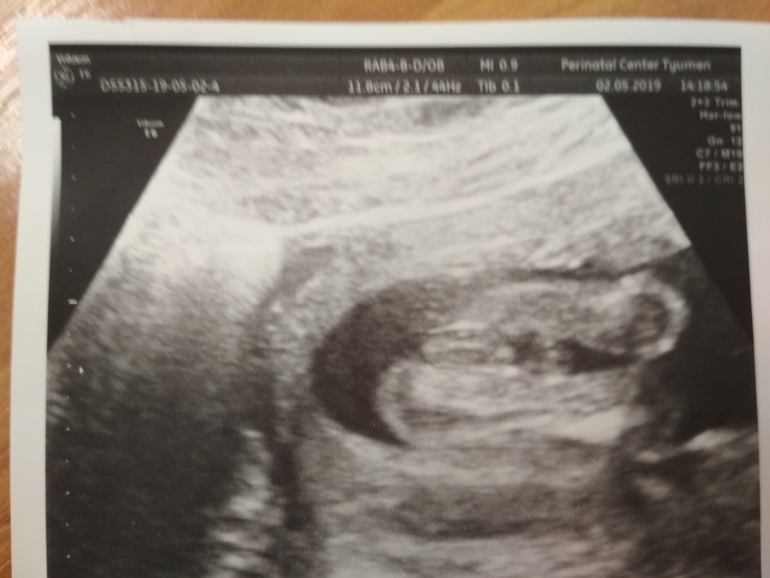

Всем привет! Немного предыстории... На первом скрининге не стали узнавать пол ребенка, сходили на 15нед. платно. Малыш прятался, но врач все же сказала девочка. Мы с мужем конечно рады и девочке. Стали имя выбирать, присматривать вещи, коляску, кроватку и др. Но когда сходили на второй скрининг, нам сказали, что мальчик. Ребеночек первый и очень долгожданный, но как теперь перенастроиться? Мы ее Ксюшенька дочка, а там и не Ксюшенька, а сынулька.... Да и вообще кому верить? Прикрепляю фото 2 скрининга.

я вот тоже думала девочка, а в 16 недель вот что))) спрашивала тут у опытных мамочек не изменится вдруг что ко 2 скринингу))) но на скрининге он вообще не показал себя)) пойду теперь в 27 неделек хочу 3д посмотреть)